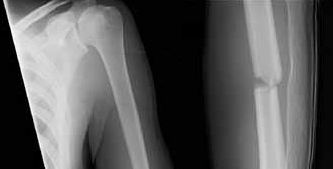

According to recent quantitative anatomical studies utilizing MRI and gadolinium, which of the following vessels provides the principal intraosseous blood supply to the humeral head, challenging historical teachings regarding proximal humerus vascularity?

Correct Answer: Posterior humeral circumflex artery

Explanation:

Historically, the anterior humeral circumflex artery (via its arcuate branch) was thought to be the primary blood supply to the humeral head. However, modern quantitative studies (e.g., Hettrich et al.) have demonstrated that the posterior humeral circumflex artery provides the vast majority (approximately 64%) of the intraosseous blood supply to the humeral head.